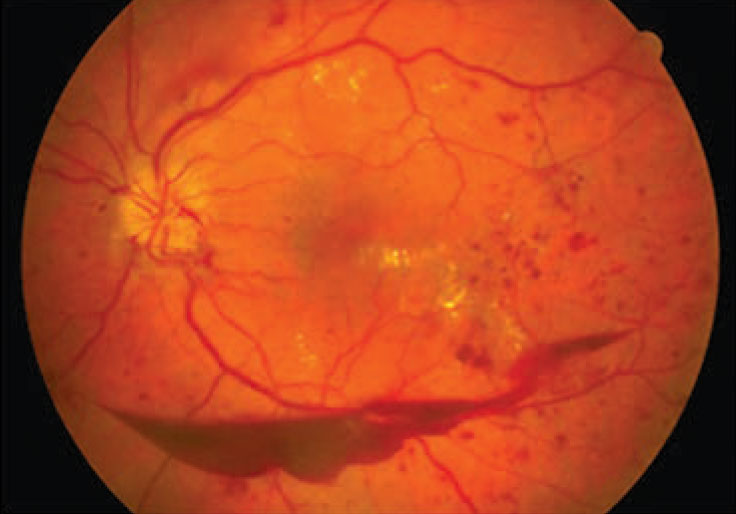

![]() Figure 1. Moderate nonproliferative diabetic retinopathy, shown here with macular edema, was found to carry a 92 percent greater risk for myocardial infarction and a 90 percent greater risk for development of congestive heart failure. (Courtesy Nidhi Relhan Batra, MD) |

Our study analyzed the five-year outcomes of patients who received DR screening in our telemedicine program. We graded retinopathy severity based on 45-degree fundus photos, with the highest degree of retinopathy between the two eyes chosen for analysis. We divided severity into four categories: no retinopathy; minimal nonproliferative diabetic retinopathy; moderate-to-severe NPDR (Figure 1); and proliferative diabetic retinopathy (Figure 2,).

Moderate-to-severe NPDR: MI (HR, 1.92; 95% CI, 1.57-2.34); CHF (HR, 1.90; 95% CI, 1.66-2.18); CVA (HR, 1.56; 95% CI, 1.29-1.89); and all-cause mortality (HR, 1.55; 95% CI, 1.32-1.82).